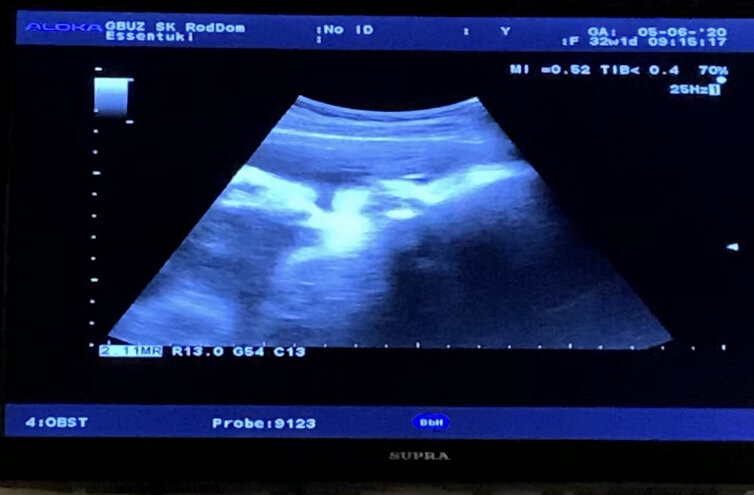

Да да, это я. Такой маленький...